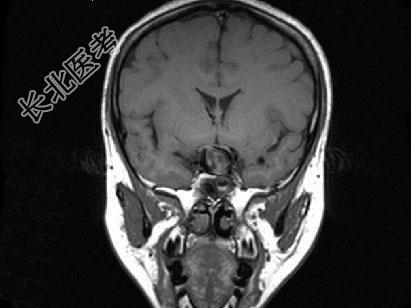

- 单项选择题女,43岁, 反复头痛10个月,CT检查如图, 最可能的诊断是 ( )